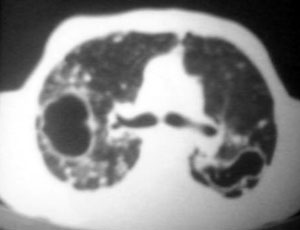

以下是引用逸风在2006-9-12 14:57:00的发言:[br]ct显示双肺上叶点片状及纤维索条状密度不均影,肺野外带近胸膜可见大小不等的含气空腔,壁略厚,境界清晰,未见液平面,中下肺野散在小片状及点状高密度影;纵隔内显示点状钙化,未见明显淋巴结肿大,构成胸廓诸骨未见明显异常.[br]诊断意见:1.双肺结核合并支气管播散;2.双肺上肺大泡.